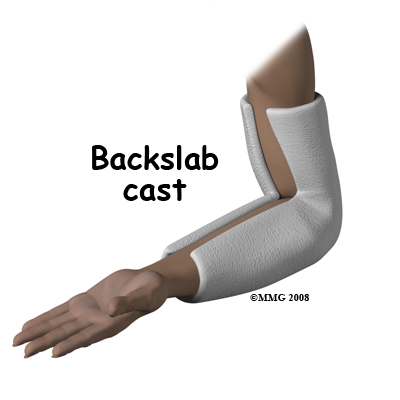

For the reasons outlined above, surgery is often the treatment of choice for many elbow fractures. However, some elbow fractures do not require surgery and can be treated in a cast. Non-displaced fractures of the medial epicondyle, lateral epicondyle, or the coronoid process can be treated in a cast, as can fractures of the radial head or radial neck that are minimally displaced. The cast serves to protect and immobilize the joint until healing reaches a stage where it is safe to begin elbow movement.

The cast is usually applied from above the elbow to the wrist. If it is necessary or desirable to prevent rotation of the forearm then the wrist should be included in the cast. Often this is not necessary and a simple splint bent at the elbow is enough. There are also many commercially available braces that can be used in place of a cast. Braces and splints allow the arm and elbow to swell without getting compressed inside the cast.